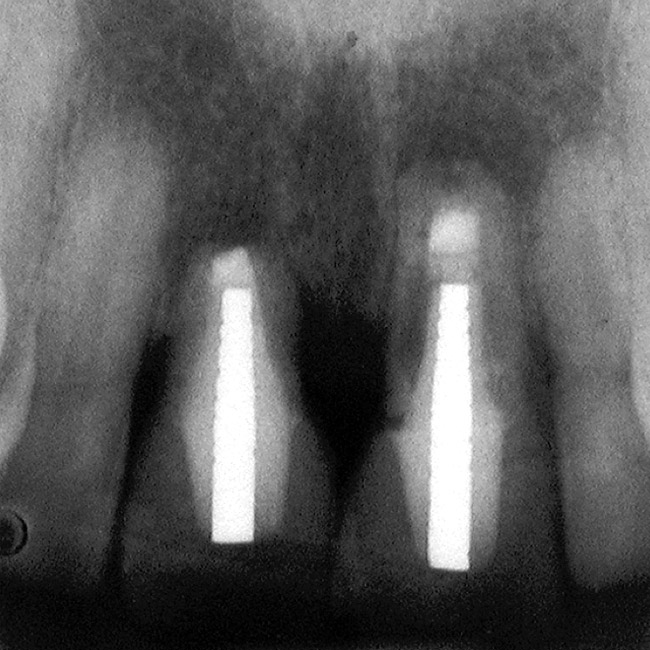

Figure 1  The relationship of the interproximal papilla height to the interproximal bone of the adjacent tooth is 4.5 mm.

Figure 1

Accounting for this difference are the biology of the periodontium and the response of the bone and soft tissues when one tooth is lost rather than multiple teeth. In the case of a single-tooth loss, if a single-tooth implant is placed, the interproximal papilla levels will be determined by the height of the interproximal bone on the adjacent natural teeth, not the interproximal bone on the implant.1-3 In the average patient, the papilla height will be 4 mm to 4.5 mm above the interproximal bone on the adjacent natural teeth (Figure 1). Therefore, if the natural teeth have no bone loss, the papilla height after tooth loss will be similar to what it was before tooth removal because the average papilla height above bone between natural teeth is also 4.5 mm.4,5 The facial gingival margin around the implant, however, is not related to the bone on the adjacent natural teeth, but rather to the facial bone levels on the implant, as well as the thickness and position of the free gingival margin before tooth removal.6,7 For a single anterior implant, the least predictable soft-tissue outcome results when the adjacent natural teeth have interproximal bone loss because managing the papilla heights can be difficult.